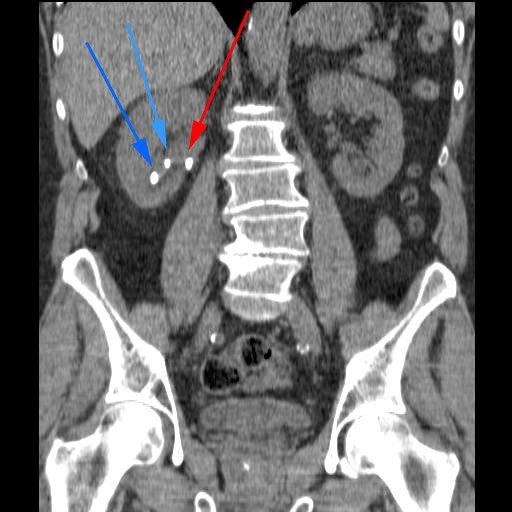

Sjokkbølgebehandling benyttes som behandling av nyrestein beliggende i nyrebekkenet eller i urinlederen. Metoden er blitt den viktigste kirurgiske behandlingen av nyrestein.

I prinsippet kan stein i alle deler av de øvre urinveier behandles. Den ideelle situasjonen er stein i nyren med samlet steinmasse mindre enn 2,5 cm i diameter, eller stein i øvre eller nedre del av urinlederen (ureter) når det ellers er normale forhold i urinveiene.